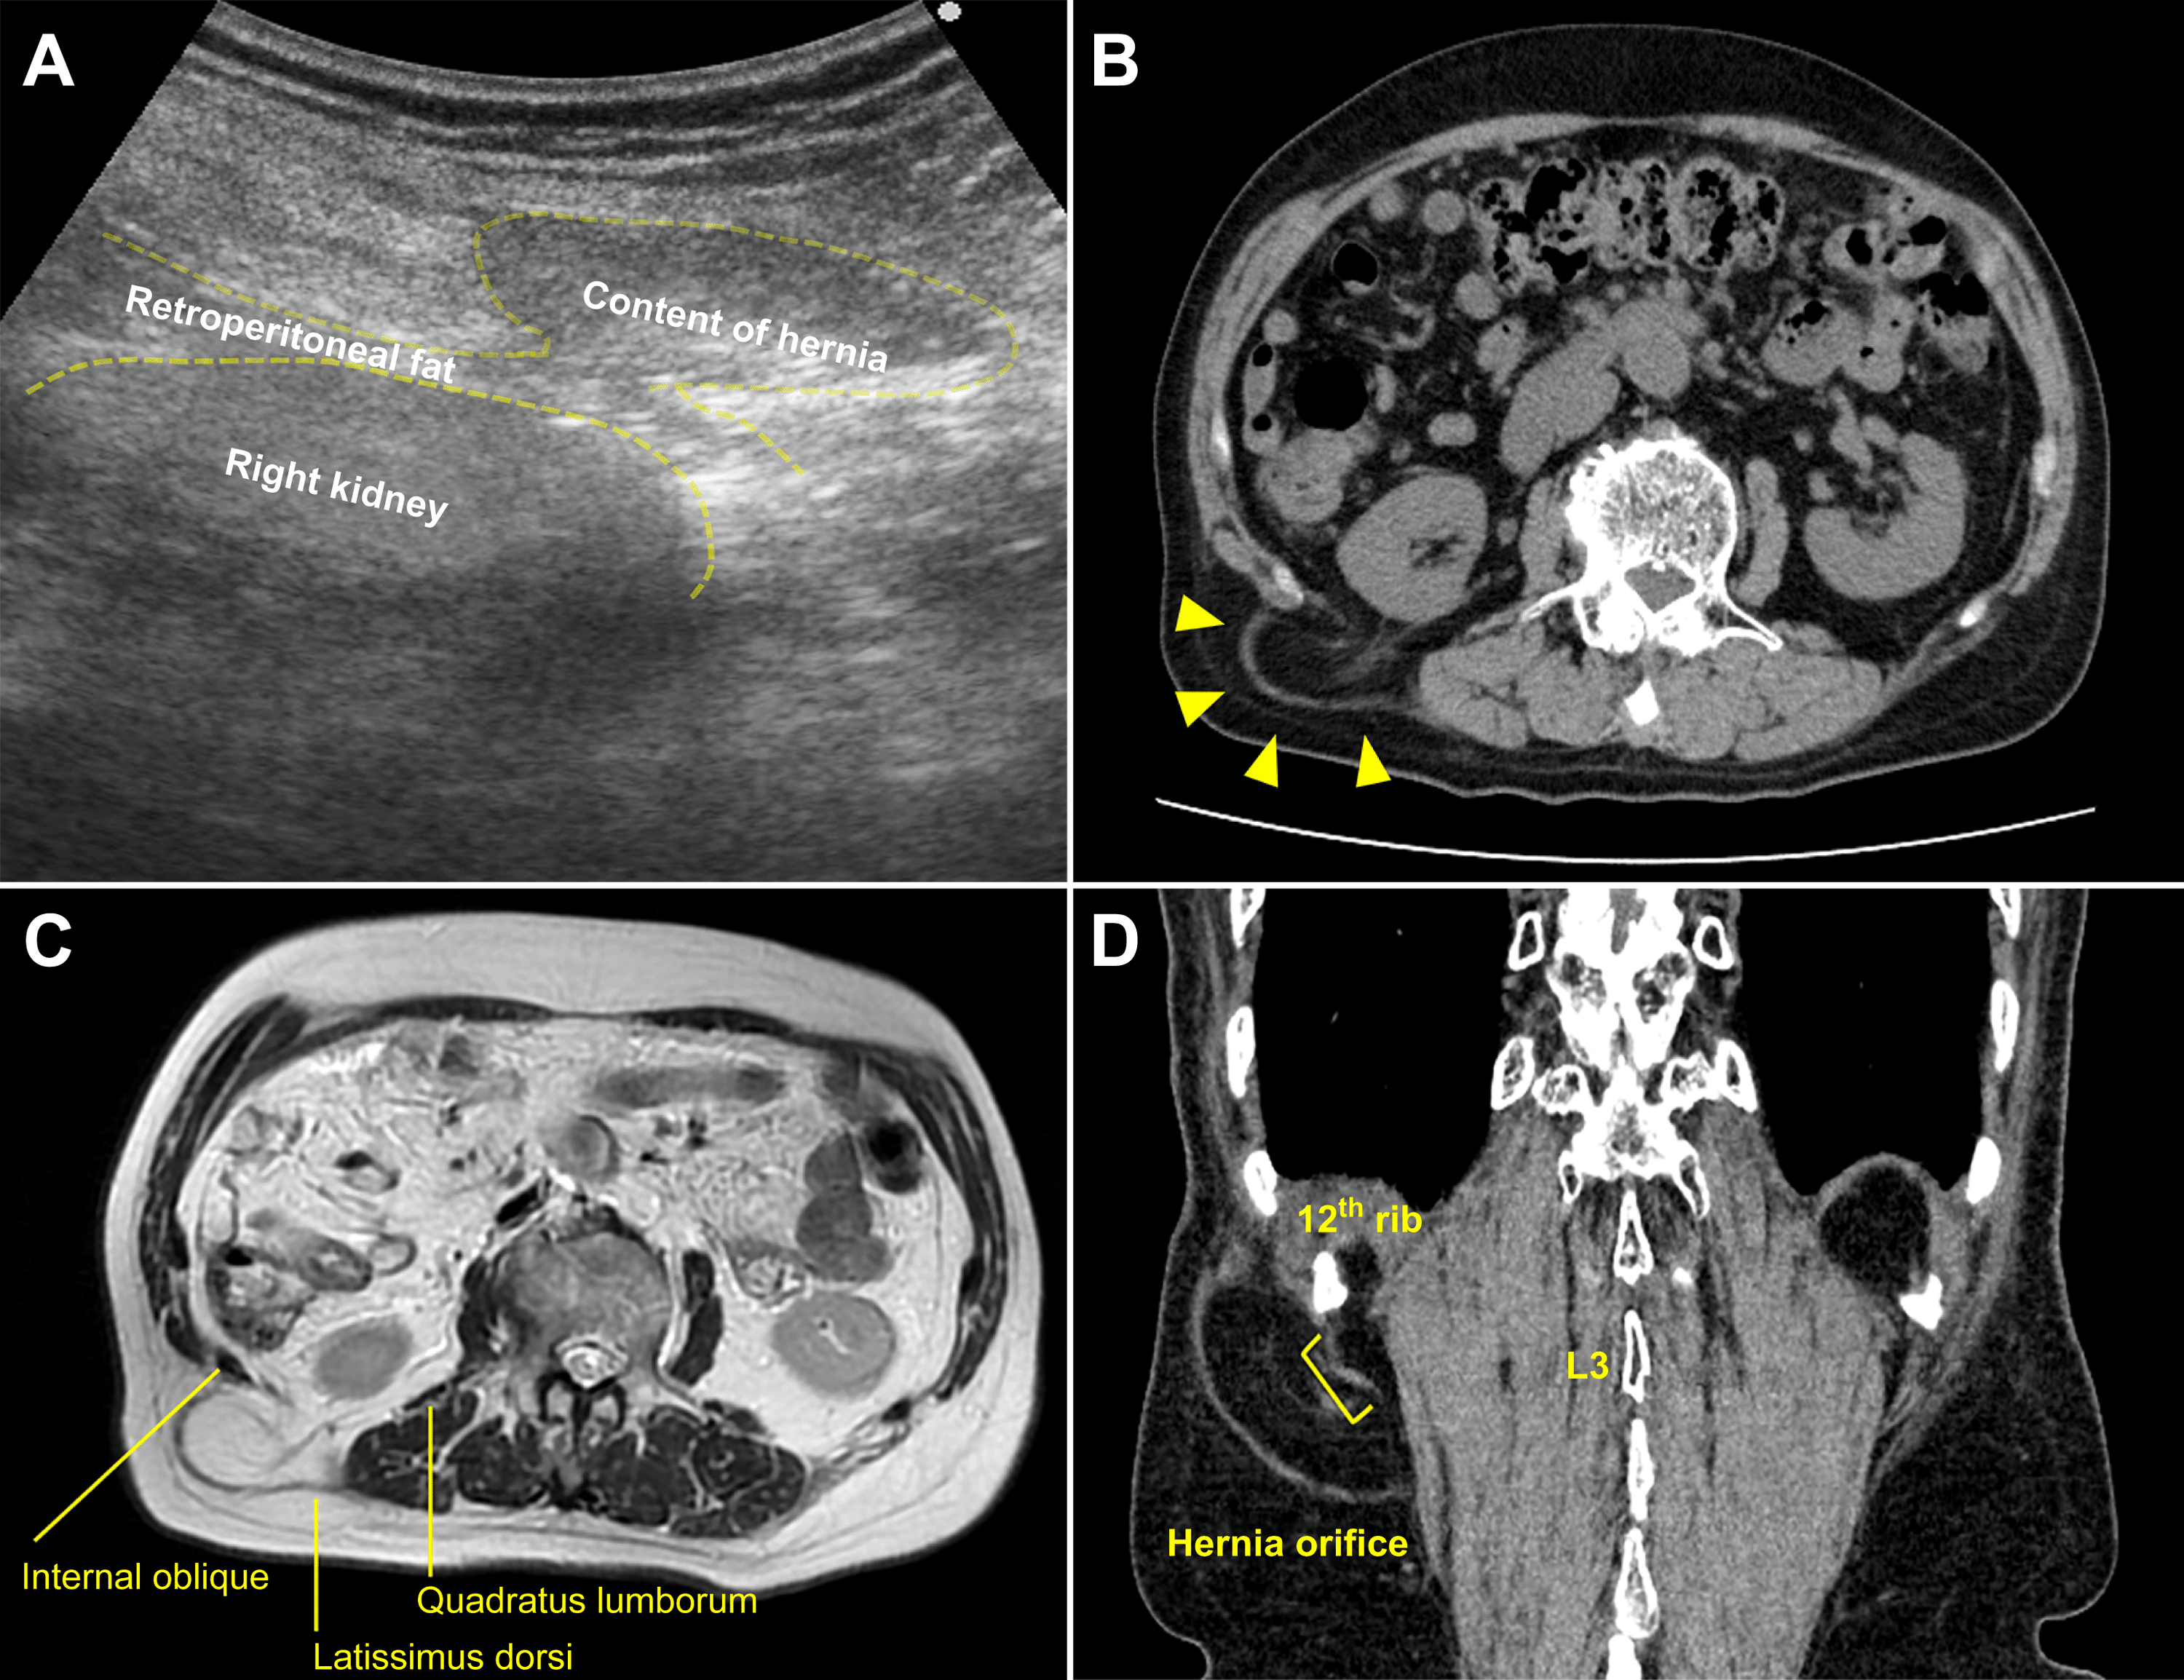

Cureus Identifying the Hernial Orifice in Superior Lumbar Hernia

Cureus Identifying the Hernial Orifice in Superior Lumbar Hernia Lumbar Hernia Ct A computed tomography (ct) scan is one of the most reliable imaging tools for diagnosing lumbar hernias. Two types are described, according to the anatomical. A computed tomography (ct) scan with myelogram is performed on patients who are unable to have an mri. We present the ct findings of seven lumbar hernias: This article covers disc herniation, facet arthrosis, synovial. Lumbar Hernia Ct.

Cureus Identifying the Hernial Orifice in Superior Lumbar Hernia Lumbar Hernia Ct Learn about the imaging features of complex abdominal wall hernias, including primary and incisional lumbar hernias. Learn how to diagnose nerve compression in the lumbar region with mri. Lumbar hernias occur through defects in the lumbar muscles or the posterior fascia, below the 12 th rib and above the iliac crest. A computed tomography (ct) scan with myelogram is performed. Lumbar Hernia Ct.

Lumbar hernia. (a) Axial computed tomography (CT) demonstrating Lumbar Hernia Ct The gold standard for the diagnosis of a lumbar hernia is performing a ct scan, with. Two types are described, according to the anatomical. Learn how to diagnose nerve compression in the lumbar region with mri. Find out how to measure the defect size, location, and loss of. Ct myelography is useful in evaluating soft tissues such. Six traumatic (four. Lumbar Hernia Ct.